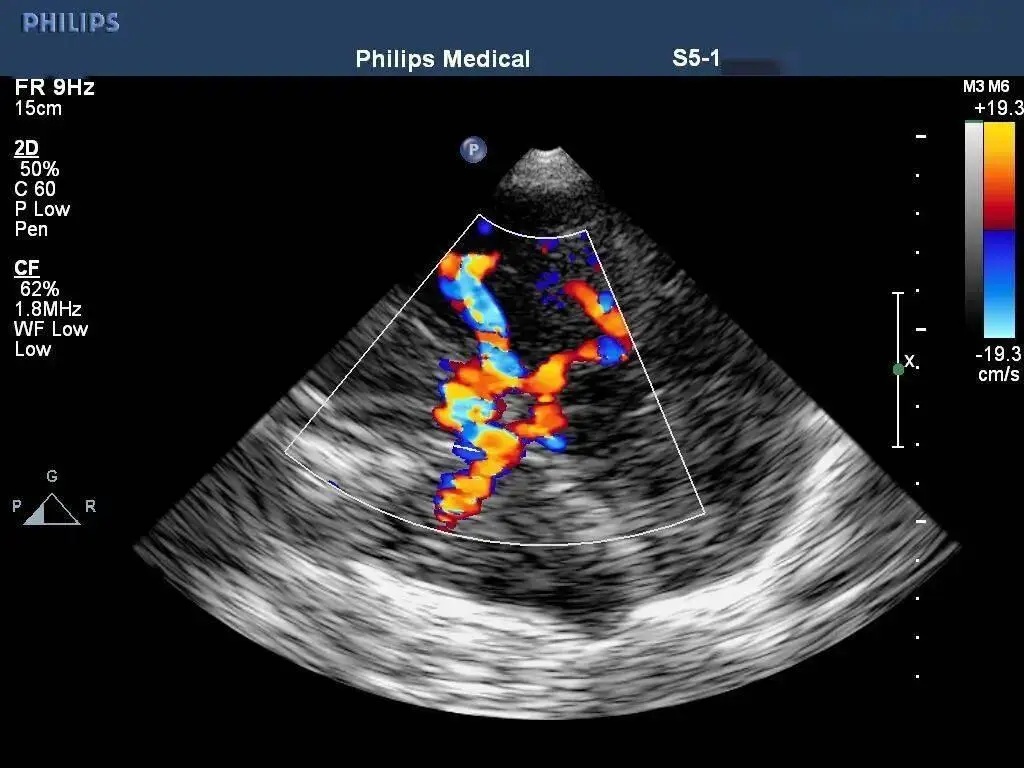

“无脉症”?颈脑血管超声联合检查,揪出血管的“窃血贼”——超...